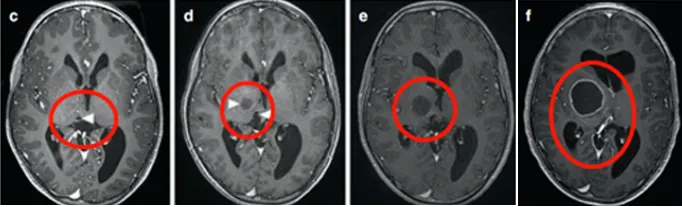

由于症状轻微而手术风险过高,术后可能较现状更差,医生评估认为不具备手术指征。然而肿瘤持续生长并形成多个小囊肿。同侧内囊(负责肢体运动功能)向前外侧移位,导致患儿从左上肢震颤进展为急性偏瘫。

马修首先接受神经导航和超声引导下活检,病理证实为WHO I级毛细胞星形细胞瘤。为治疗多发性囊肿,就诊于INC鲁特卡教授后植入Ommaya囊,并在超声引导下将导管置入肿瘤囊性成分。MRI复查显示囊性占位解除,脑室形态逐渐恢复正常。

4个月后偏瘫症状未改善,鲁特卡教授又为其行经胼胝体半球间入路肿瘤切除术,成功切除肿瘤。术后患儿偏瘫症状改善,生长发育和智力发育均恢复正常水平。